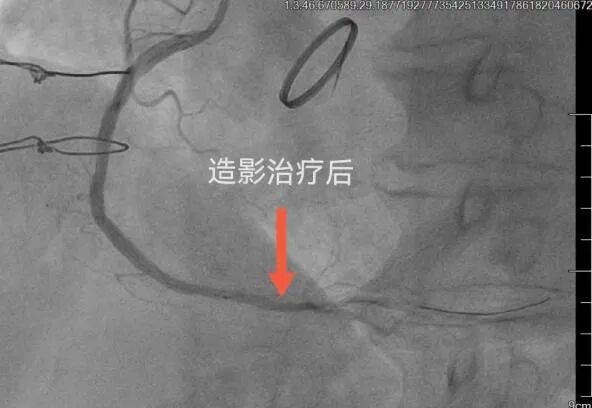

1月8日,心病科团队经过前期的周密准备,为杨大爷制定了详细的手术方案。当天,李爱勇主任及其介入团队为患者顺利实施了冠脉介入手术,成功进行了药物球囊扩张术,开通了杨大爷心脏堵塞的血管,为杨大爷带来了重获新生的希望。整个手术过程持续了2个多小时,手术一开始因患者右侧桡动脉明显迂曲给穿刺带来了极大的困难,但李主任考虑患者之前股动脉造影时不良后果明显,经过耐心尝试最终顺利完成桡动脉穿刺达到造影指定位置,之后手术进行顺利,杨大爷全程意识清晰,术后杨大爷胸闷气短等症状明显缓解,目前恢复良好。